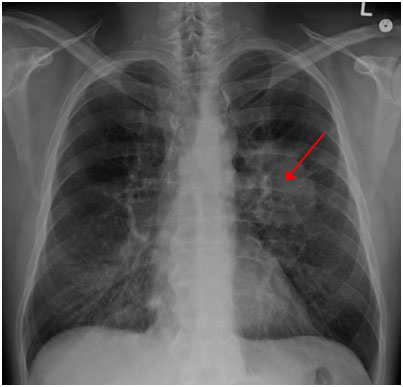

圖示:胸片上可見肺癌。(來源:James Heilman醫(yī)學(xué)博士/維基百科)